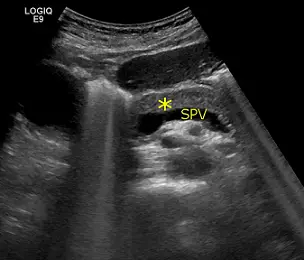

附圖為腹部超音波, SPV 是脾靜脈,星號為下列何者構造?

本題附圖為腹部超音波影像(機型:LOGIQ E9),橫斷面(transverse)掃描視野。影像右側標示 SPV(脾靜脈),呈管狀低回聲(anechoic)結構,為重要的解剖標誌。影像左側的黃色星號(*)標示一塊相對均質、回聲稍強的實質性構造,位於脾靜脈的前方(anterior),且回聲較周遭結構略高。

根據腹部超音波解剖原則:

- 胰臟體部/尾部在橫切面上恆位於脾靜脈前方

- 脾靜脈沿胰臟後緣(posterior border)從脾臟走向中線,再與腸繫膜上靜脈(superior mesenteric vein, SMV)匯合形成門靜脈(portal vein)

- 胰臟在超音波上呈均質等回聲至高回聲(isoechoic to hyperechoic),回聲強度與肝臟相近或略高

因此,星號(*)所指之構造即為胰臟(pancreas),正確答案為 (D)。